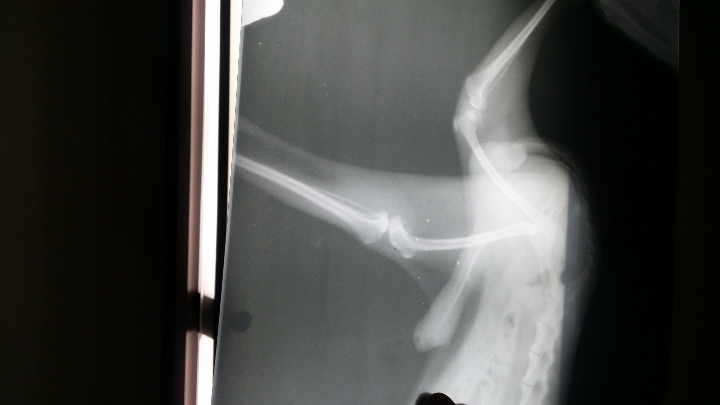

狗狗髌骨二期,这种病是一种罕见的遗传病,患病率仅为千分之一。